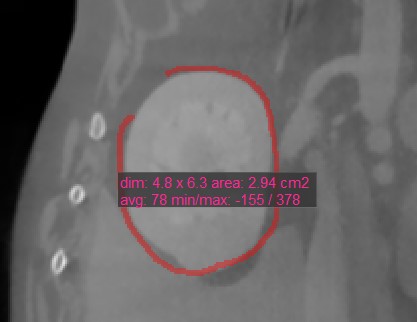

Polygon¶

Users can create, measure and mark custom rounded areas on the active image slice by using the Polygon

tool.

Select the Polygon

tool and assign it to one of the available mouse buttons. Start the measurement by placing points on the active image slice. As the user places the points, the software automatically connects them

and creates the rounded shape.

Complete the measurement by manually closing the path, or double-click when placing the last point to automatically close it. All available measurement values are displayed alongside the measurement.

Modify the marked area by moving one of the points describing the shape using the Default